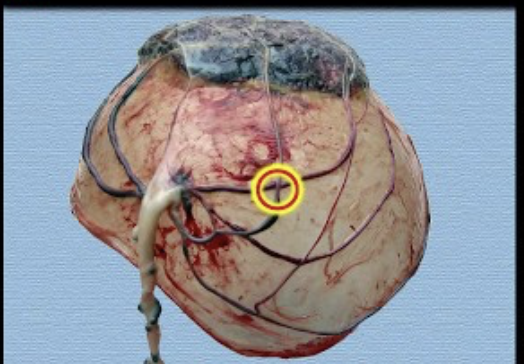

What type of vasa praevia is depicted? [1]

A